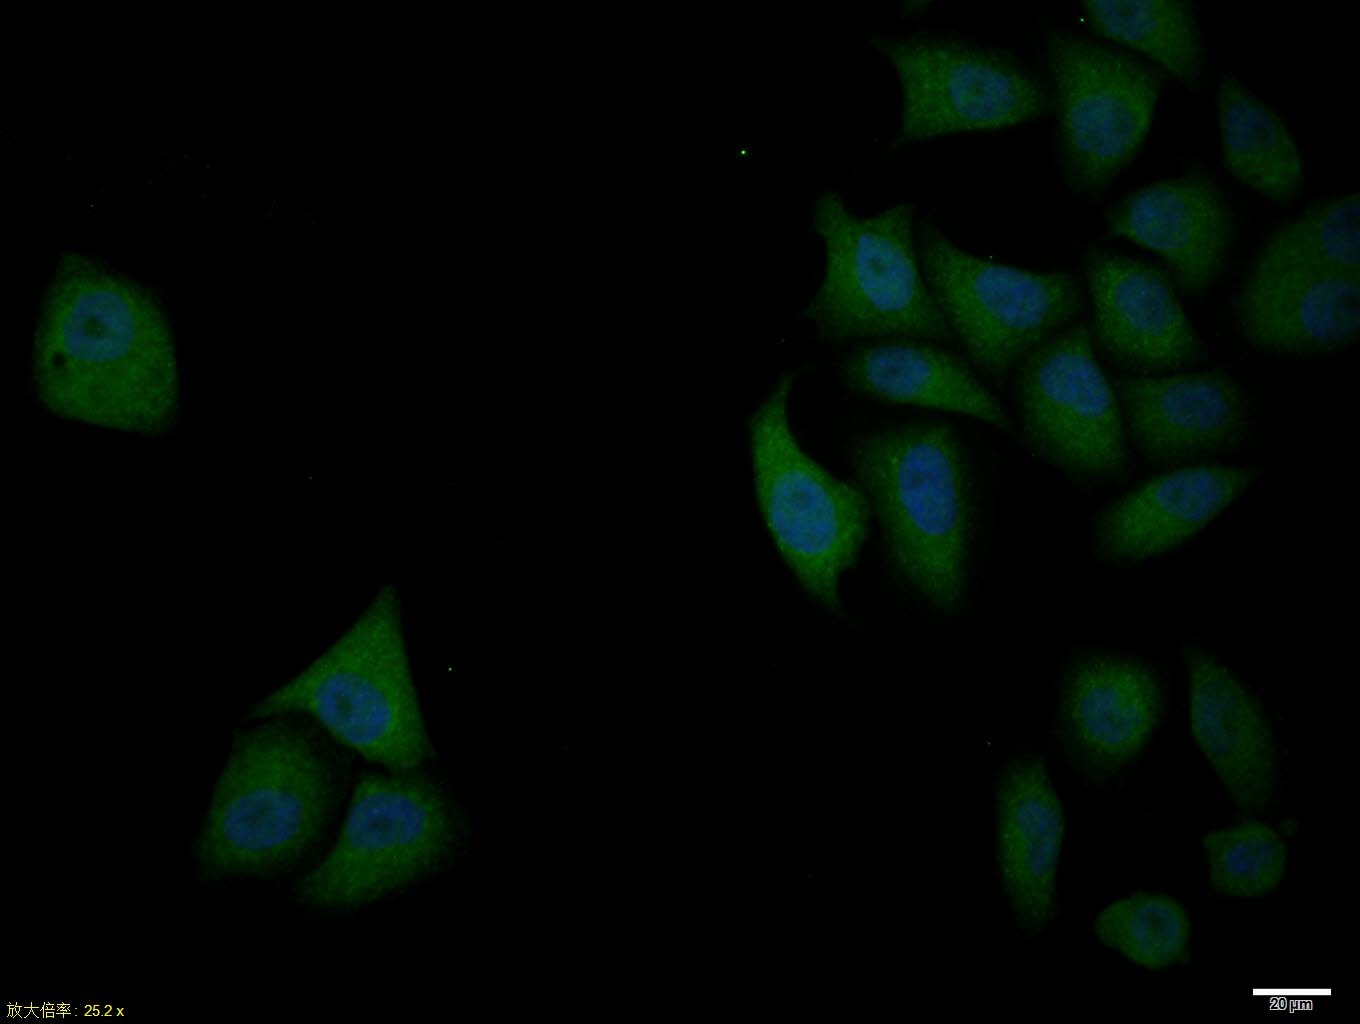

| Verified Activity | 1. Paraformaldehyde-fixed, paraffin embedded (mouse brain tissue); Antigen retrieval by boiling in sodium citrate buffer (pH6.0) for 15 min; Block endogenous peroxidase by 3% hydrogen peroxide for 20 min; Blocking buffer (normal goat serum) at 37°C for 30 min; Antibody incubation with (Bcl-xL) Polyclonal Antibody, Unconjugated (TMAB-00202) at 1:400 overnight at 4°C, followed by operating according to SP Kit (Rabbit) instructionsand DAB staining. 2. Paraformaldehyde-fixed, paraffin embedded (mouse testis tissue); Antigen retrieval by boiling in sodium citrate buffer (pH6.0) for 15 min; Block endogenous peroxidase by 3% hydrogen peroxide for 20 min; Blocking buffer (normal goat serum) at 37°C for 30 min; Antibody incubation with (Bcl-xL) Polyclonal Antibody, Unconjugated (TMAB-00202) at 1:400 overnight at 4°C, followed by operating according to SP Kit (Rabbit) instructionsand DAB staining. 3. Blank control: Jurkat. Primary Antibody (green line): Rabbit Anti-Bcl-xL antibody (TMAB-00202) Dilution: 1 μg/Test; Secondary Antibody: Goat anti-rabbit IgG-FITC Dilution: 0.5 μg/Test. Protocol The cells were fixed with 4% PFA (10 min at room temperature) and then permeabilized with 0.1% PBST for 20 min at room temperature. The cells were then incubated in 5% BSA to block non-specific protein-protein interactions for 30 min at room temperature. Cells stained with Primary Antibody for 30 min at room temperature. The secondary antibody used for 40 min at room temperature. 4. Hela cell; 4% Paraformaldehyde-fixed; Triton X-100 at room temperature for 20 min; Blocking buffer (normal goat serum) at 37°C for 20 min; Antibody incubation with (Bcl-xL) polyclonal Antibody, Unconjugated (TMAB-00202) 1:100, 90 minutes at 37°C; followed by a conjugated Goat Anti-Rabbit IgG antibody at 37°C for 90 minutes, DAPI (blue) was used to stain the cell nucleus. 5. Blank control: A431. Primary Antibody (green line): Rabbit Anti-Bcl-xL antibody (TMAB-00202) Dilution: 1 μg/10^6 cells; Isotype Control Antibody (orange line): Rabbit IgG. Secondary Antibody: Goat anti-rabbit IgG-AF647 Dilution: 1 μg/test. Protocol The cells were fixed with 4% PFA (10 min at room temperature) and then permeabilized with 90% ice-cold methanol for 20 min at-20°C. The cells were then incubated in 5% BSA to block non-specific protein-protein interactions for 30 min at at room temperature. Cells stained with Primary Antibody for 30 min at room temperature. The secondary antibody used for 40 min at room temperature. ![]() ![]() ![]() ![]() ![]() |